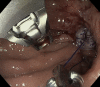

Endoscopic closure of a refractory enterocutaneous fistula by use of a fistula plug with fixation and mucosal oversewing